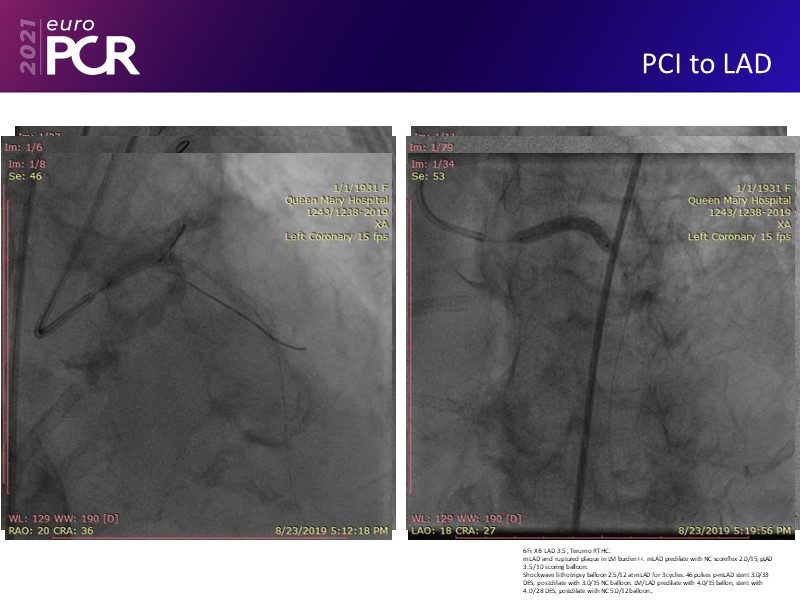

Leave no calcium uncracked--triple vessel disease, severe AS, cardiogenic shock EuroPCR 2021 Clinical Case SPEAKER: J. Fang Previous Next Download presentation